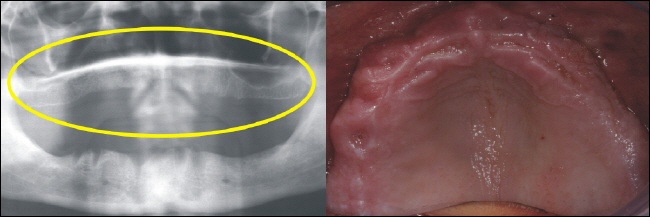

Das Bild rechts zeigt den zahnlosen Oberkiefer. Im Röntgenbild sieht dies aus wie auf dem linken Bild (gelber Kreise). |

Der zahnlose Unterkiefer rechts im Bild bietet keinen Halt mehr für eine Prothese. Links zeigt sich der zahnlose Knochenabschnitt im Röntgenbild (gelber Kreis). |